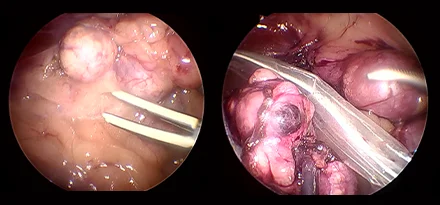

복강경

기존의 개복수술은 충분한 노출을 위하여 복부의 피부와 복벽 근육을 길게 절개해야 합니다.

하지만 복강경을 이용하면 보통 3mm-10mm 직경의 포트를 통해 복강 내에 이산화탄소를 주입하여 공간을 만들고,

카메라를 통해 더 뚜렷하게 시각화할 수 있고 지혈 기구를 통해 장기들을 안전하게 분리하여 절제할 수 있습니다.

복강경의 경우 대형견에서 그 장점이 뚜렷하며 현재는 소형견, 고양이에서도 이러한 장점 때문에 최소 침습 수술을 진행하게 됩니다.

본원에서는 간단한 중성화나 조직생검 외에도 부신절제술, 담낭절제술, 신장절제술, 비장절제술, 간엽절제술 등을 포함한

고난도 수술도 실시합니다.

복강경신장절제술

복강경부신절제술

복강경담낭절제술

* 리본동물의료센터 케이스 사진으로 무단 복제 및 도용을 금지합니다.